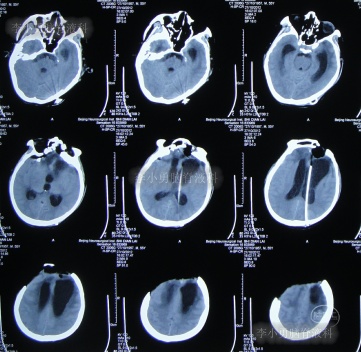

为求进一步治疗,2022年4月29日,第2次来李小勇脑脊液科治疗。入院时:意识不清,刺痛后四肢能动(图-31),查头颅CT(图-32)示脑室有扩张,有积气。

图-31:2022年4月29日入院时

图-32:2022年4月29日头颅CT

入院后当天进行了原分流管拔除术+脑室引流术,术后当天查头颅CT示有出血(图-33)。

图-33:2022年4月29日术后头颅CT

术后5天即2022年5月3日,查头颅CT示脑室有缩小(图-35)。

图-35:2022年5月3日头颅CT

2022年5月13日(入院治疗15天),查头颅CT示脑室又有缩小(图-36)。

图-36:2022年5月13日头颅CT

2022年5月23日(入院治疗25天),查头颅CT示脑室缩小(图-37)。

图-37:2022年5月23日头颅CT

脑脊液化验变正常后于2022年9月9日(治疗133天),进行了脑室腹腔分流术(图-39)。

图-39:2022年9月9日头颅CT